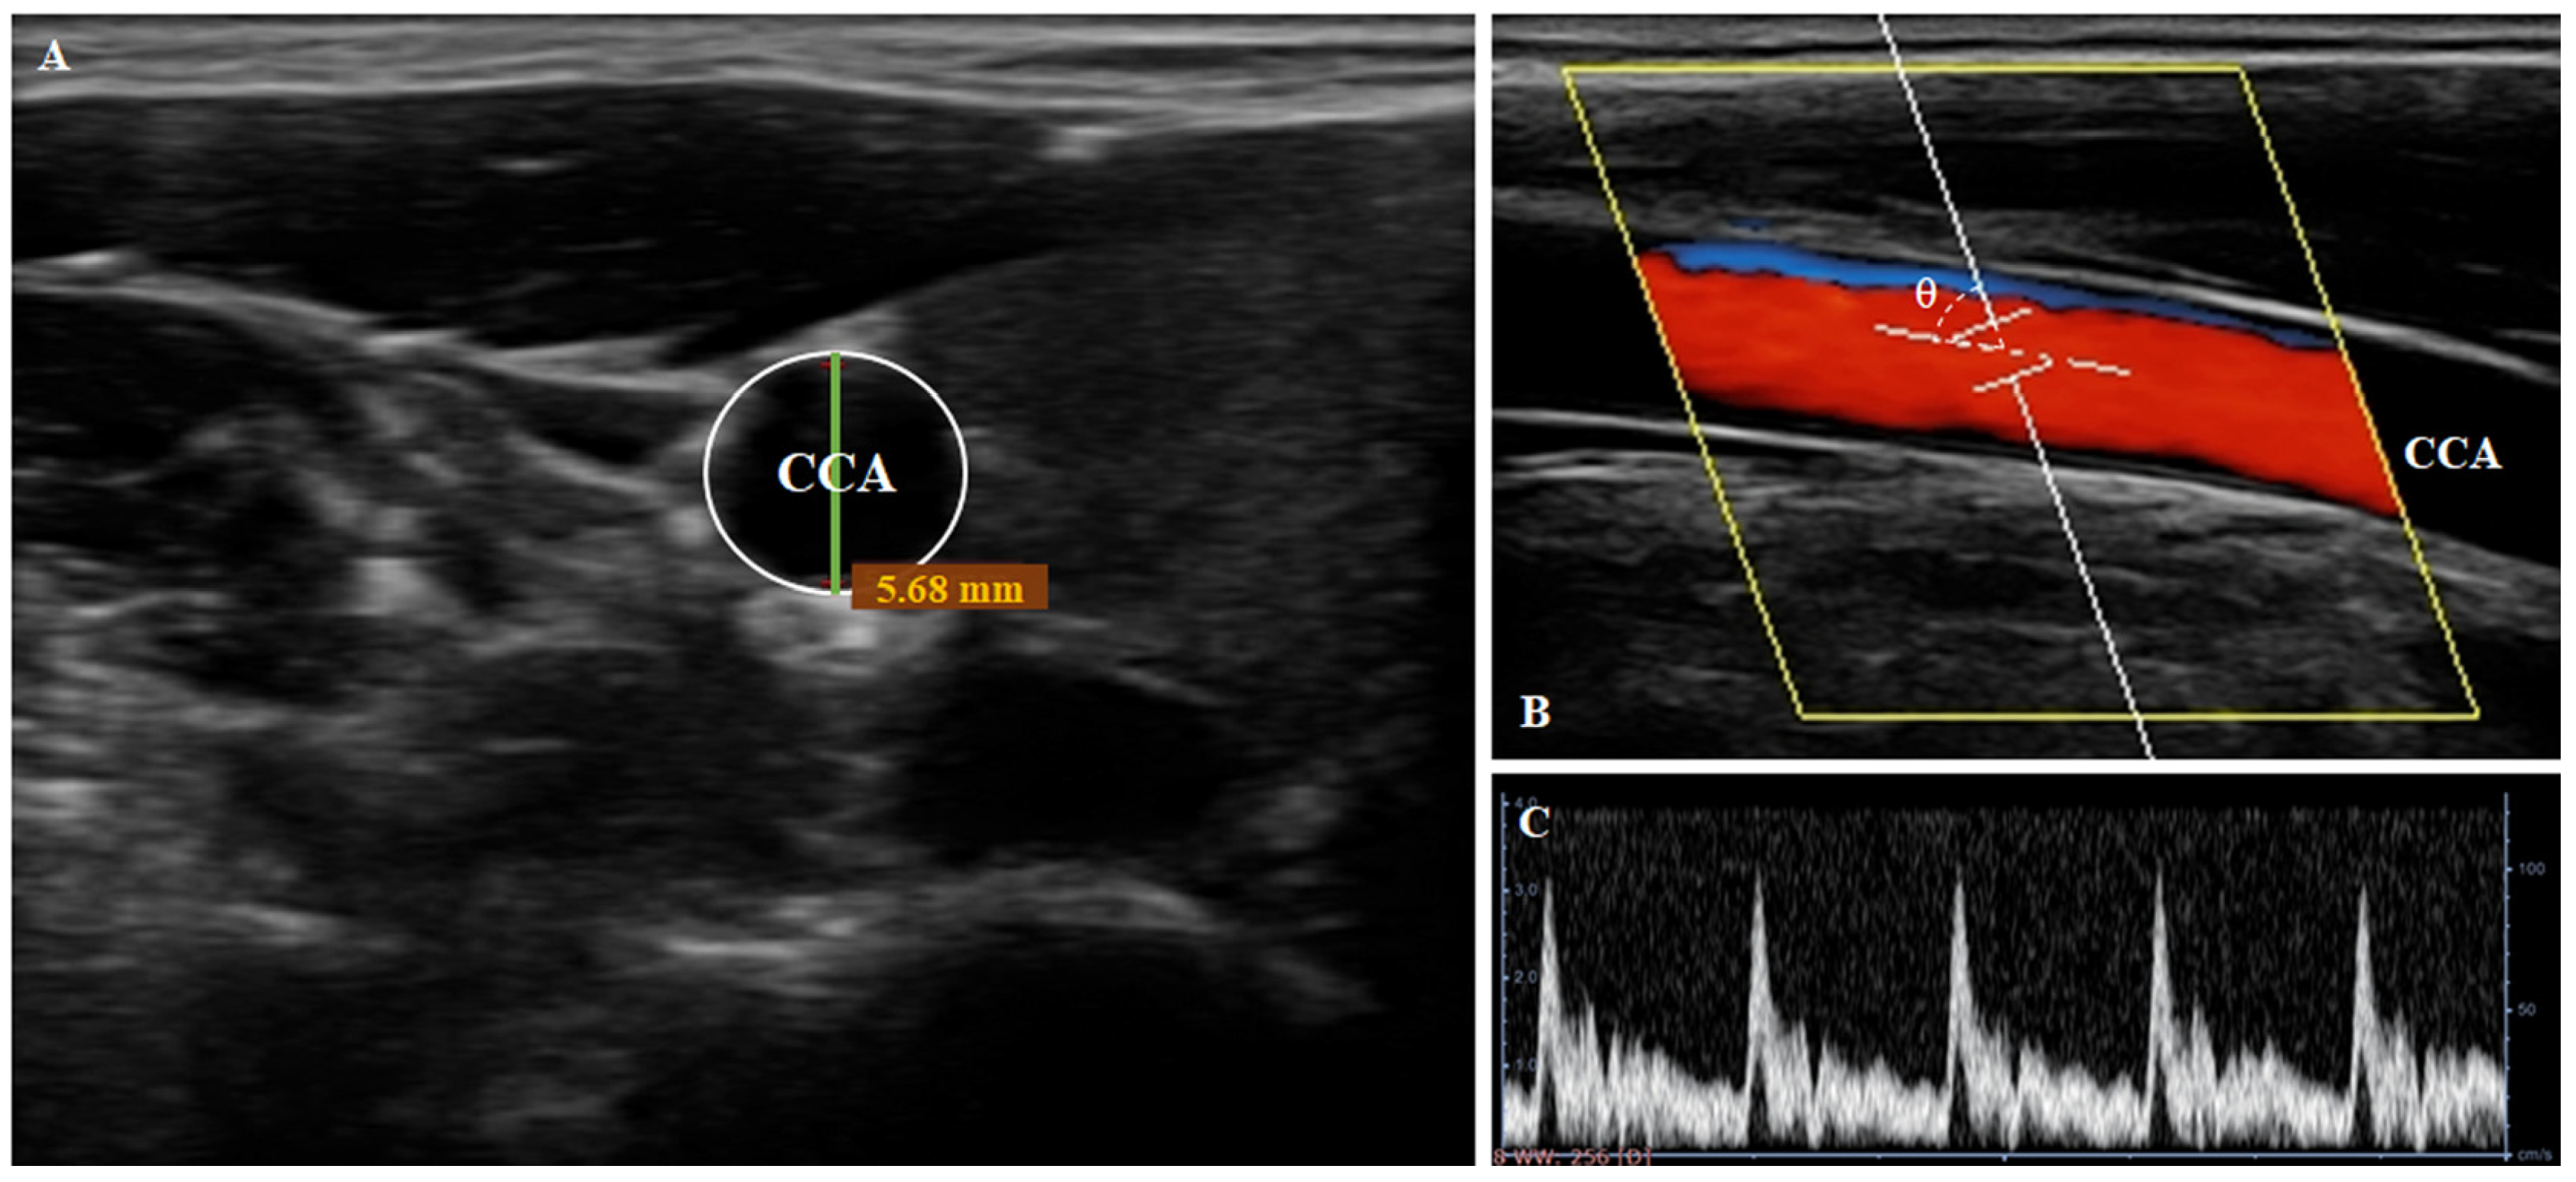

2.3.2. Vascular Hemodynamic Parameters Measurements

Carotid Pulse Wave Velocity (PWV) Measurements

Central Pulsed Doppler Measurements